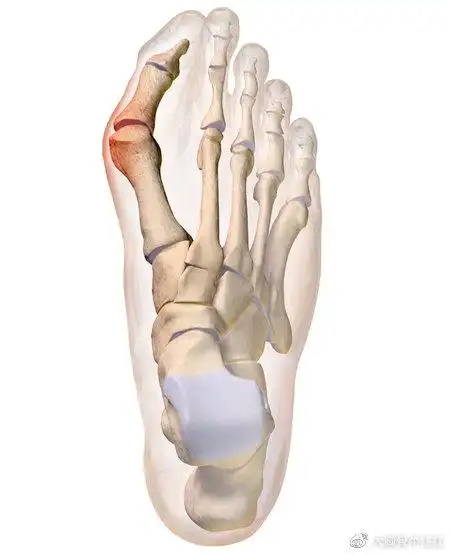

大脚拐,大脚趾内侧疼痛,要警惕:拇(趾)外翻,拇囊炎

趾骨骨折克氏针内固定手术